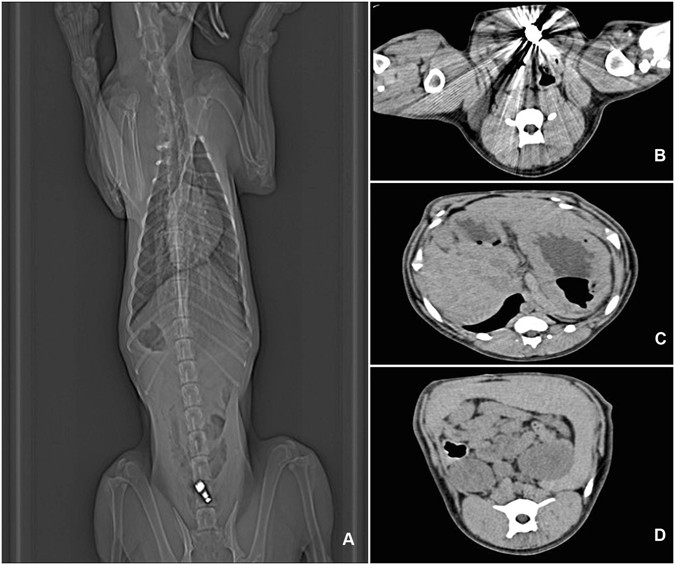

Radiographic examinations after administration of ultra-high frequency capsules. (A) Abdominal plain film after 2 hours’ vibration at ultra-high frequency. (B) CT image of stomach (arrow showing VC in the stomach). (C) CT image of intestine. (D) CT image of rectum.